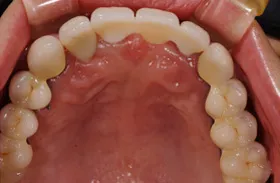

インプラント治療及び補綴治療のケース

■治療前:奥歯が無いため噛み合わせが深く下の歯が全く見えない

噛み合わせが低いため全体的に歯が削れている

■治療後:下顎 左下5・6番、右下4・6番にインプラント治療

その他の歯に補綴治療をしたことにより、奥歯もしっかりと咬むことができ、奥歯ができたことにより噛み合わせも上がって下の歯も見えるようになり、審美的にも改善された

| 主訴 | 歯科治療をしても歯がすぐに欠けてしまう 奥歯が無いため、奥歯で咬めない |

| 治療方法 | インプラント治療 + 補綴治療 |

| 治療期間 | 約1年 |

| 通院回数等 | 約20回 |

| 費用 | 約250万円(税込) |

| リスク・副作用 | 術後の腫れ・痛み |